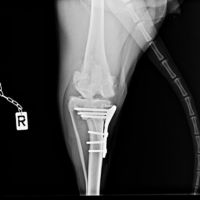

Orthopédie

L'orthopédie se consacre à l'étude des maladies de l'appareil locomoteur : os, articulations, muscles, tendons, ligaments... Chez les chiens et les chats, ces affections sont fréquentes, entrainant douleur, boiterie, difficultés pour marcher, pour sauter...

Le Dr Lionel SIMON s'intéresse particulièrement à ce domaine et sera ravi de vous recevoir sur rendez-vous.